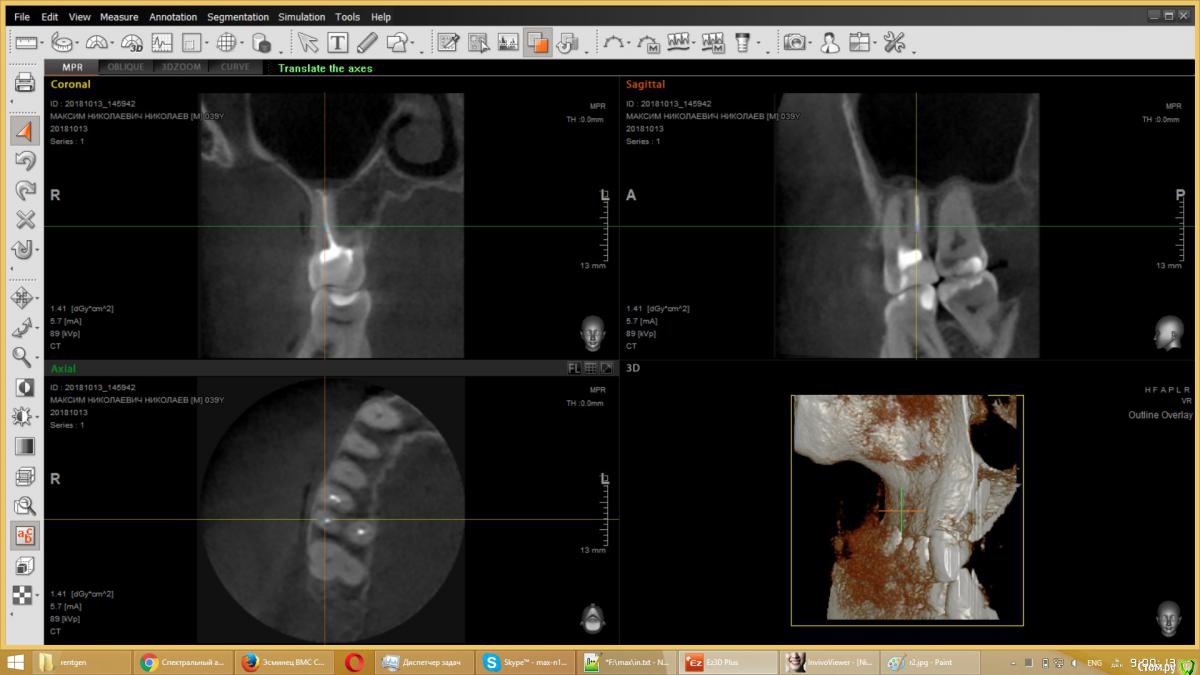

usilitel Опубликовано 4 декабря, 2018 Поделиться Опубликовано 4 декабря, 2018 (изменено) 10 месяцев назад депульпировали верхнюю 6-ку, с тех пор мучаюсь неврологическими симптомами (онемение, давление, зуд). На снимке с зубом всё нормально. Возможная причина - небольшое количество материала вышло в гайморову пазуху (но осталось под слизистой). Я думаю что этот материал мог задеть нерв, отсюда и симптомы. Зуб вырывать врачи отказываются, т.к. показаний к удалению нет. К тому же может не помочь.Хочу вынуть материал из гайморовой пазухи, но непонятно как это сделать. Прошу совета.Возможный варианты:1) Оставить всё как есть. Меня этот вариант не устраивает, т.к.: 1) материал может быть причиной проблем с неврологией, и его удаление может решить проблему. 2) зуб все равно рано или поздно придется удалять, не хотелось бы чтобы после удаления зуба в организме осталось инородное тело.2) Вынуть эндоскопом сверху. ЛОР сказал что так сделать нельзя, т.к. поскольку материал под слизистой - сверху его не увидишь. Правда можно содрать слизистую и всё-таки достать материал, но вред от такого действия многократно превысит пользу.3) При удалении зуба вынуть материал снизу. По словам хирурга - стоматолога - это сделать нереально, т.к. для этого придется разрезать перегородку, отделяющую гайморову пазуху, и она потом сама не заживёт.4) Надеяться, что матерал сам выйдет вместе с зубом при удалении зуба. Вариант крайне маловероятный, т.к. при удалении зуба материал практически наверняка останется в пазухе.5) Распломбировать канал, протолкнуть материал дальше в гайморову (чтобы он вышел за слизистую), а потом вынимать сверху эндоскопом. Не уверен что найду терапевта который согласится это сделать.6) Сразу после удаления зуба протолкнуть материал дальше в гайморову (чтобы он вышел за слизистую), а потом вынимать сверху эндоскопом. Не уверен что найду хирурга который согласится это сделать. PSЗуб мне не жалко, всё равно рано или поздно его надо будет удалять. Изменено 4 декабря, 2018 пользователем usilitel Ссылка на комментарий

usilitel Опубликовано 6 декабря, 2018 Автор Поделиться Опубликовано 6 декабря, 2018 выкладываю снимки Ссылка на комментарий